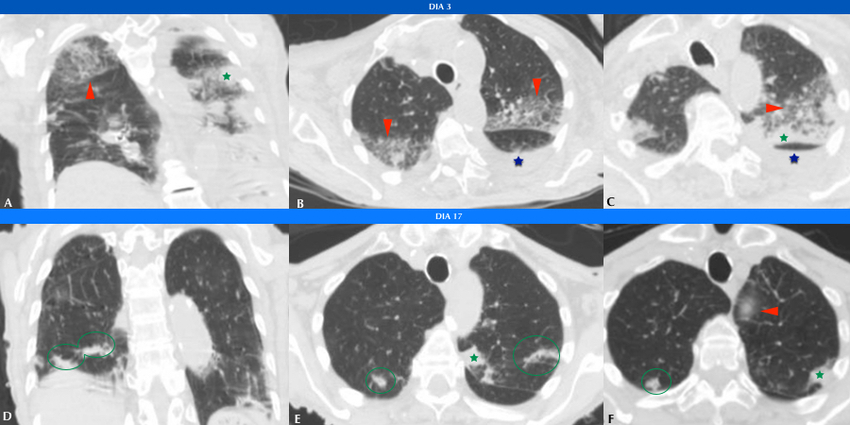

Se realizó TC de tórax a 85 (5,9%) pacientes, de los cuales 11 (13%) fueron positivos por PCR para COVID19. De estos, 9 (81%) manifestaron infiltrados en vidrio esmerilado en el parénquima pulmonar, asociándose además opacidades consolidativas en 4 (36%) de ellos (Figs. 3 y 4). 2 (18%) pacientes no mostraron afectación intersticio-alveolar en su evolución. La TC se realizó a pacientes cuya clínica no era acorde a los hallazgos de Rx y a aquellos con evolución tórpida (81%). En total, a 8 (72%) pacientes COVID-19 positivos se les realizaron ambos métodos imagenológicos.

En cuanto a la distribución, en los cortes axiales se encontró que siete pacientes presentaron opacidades o consolidaciones periféricas, o ambas (Figs. 5 y 6).

La cantidad de lóbulos afectados fue variable. Un paciente presentó afectación lobar única, uno afectación bilobar, cuatro afectación de tres lóbulos y dos pacientes de cuatro lóbulos. Únicamente un paciente sufrió compromiso panlobar (Fig. 7). Los lóbulos pulmonares con mayor afectación fueron los superiores: siete pacientes tuvieron afectación del lóbulo superior derecho y ocho pacientes del lóbulo superior izquierdo. Cabe mencionar, además, que ocho pacientes tuvieron afectación bilateral y uno unilateral.

En un paciente se encontró patrón en empedrado (Fig. 8) y en dos pacientes opacidades redondeadas en vidrio esmerilado (Tabla 1).

Como hallazgos atípicos, se evidenciaron derrame pleural en dos pacientes y neumotórax en uno, cuya causa fue atribuida a complicación tras la colocación de un marcapasos (Fig. 9). No se evidenciaron adenomegalias mediastinales.